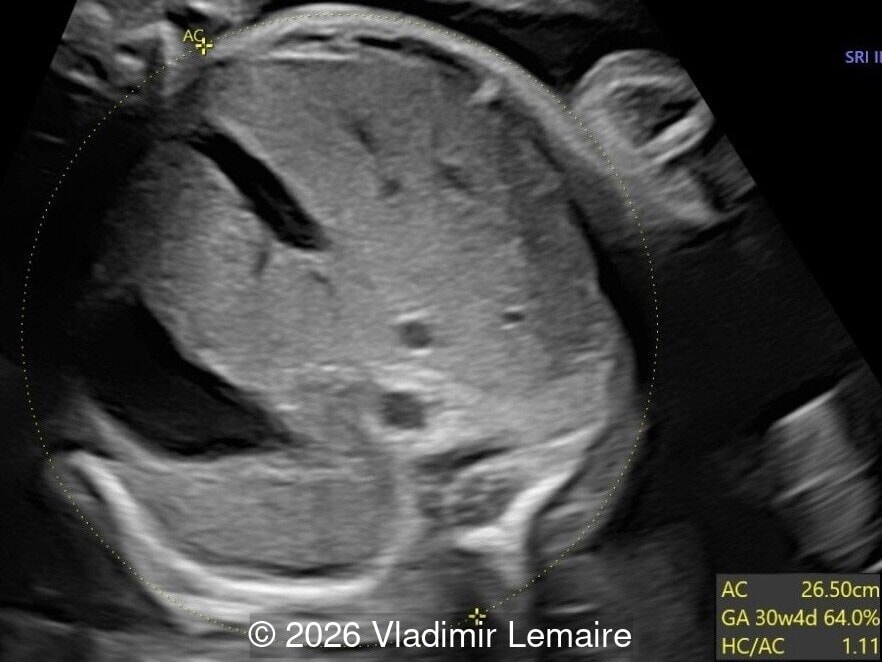

Transverse view of the upper abdomen at the level of the abdominal circumference.

Image 1 Transverse view of the upper abdomen at the level of the abdominal circumference.